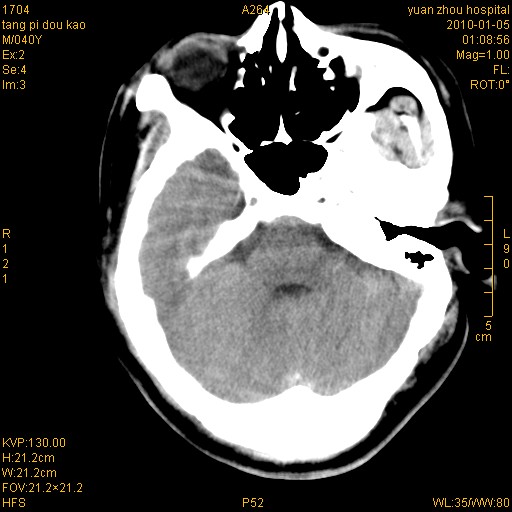

标题: CT23986:M 40Y 外伤数小时

挫伤血肿形成   还有一个左枕部硬膜外血肿考虑

1)左侧颞枕部硬膜外血肿。2)右侧额部硬膜下血肿。3)双侧额叶及右侧基底节下部脑挫裂伤。4)蛛网膜下腔出血。5)脑水肿。6)左侧前组筛窦及左侧额窦炎症。

+左侧颧骨骨折。

左侧颧骨骨折